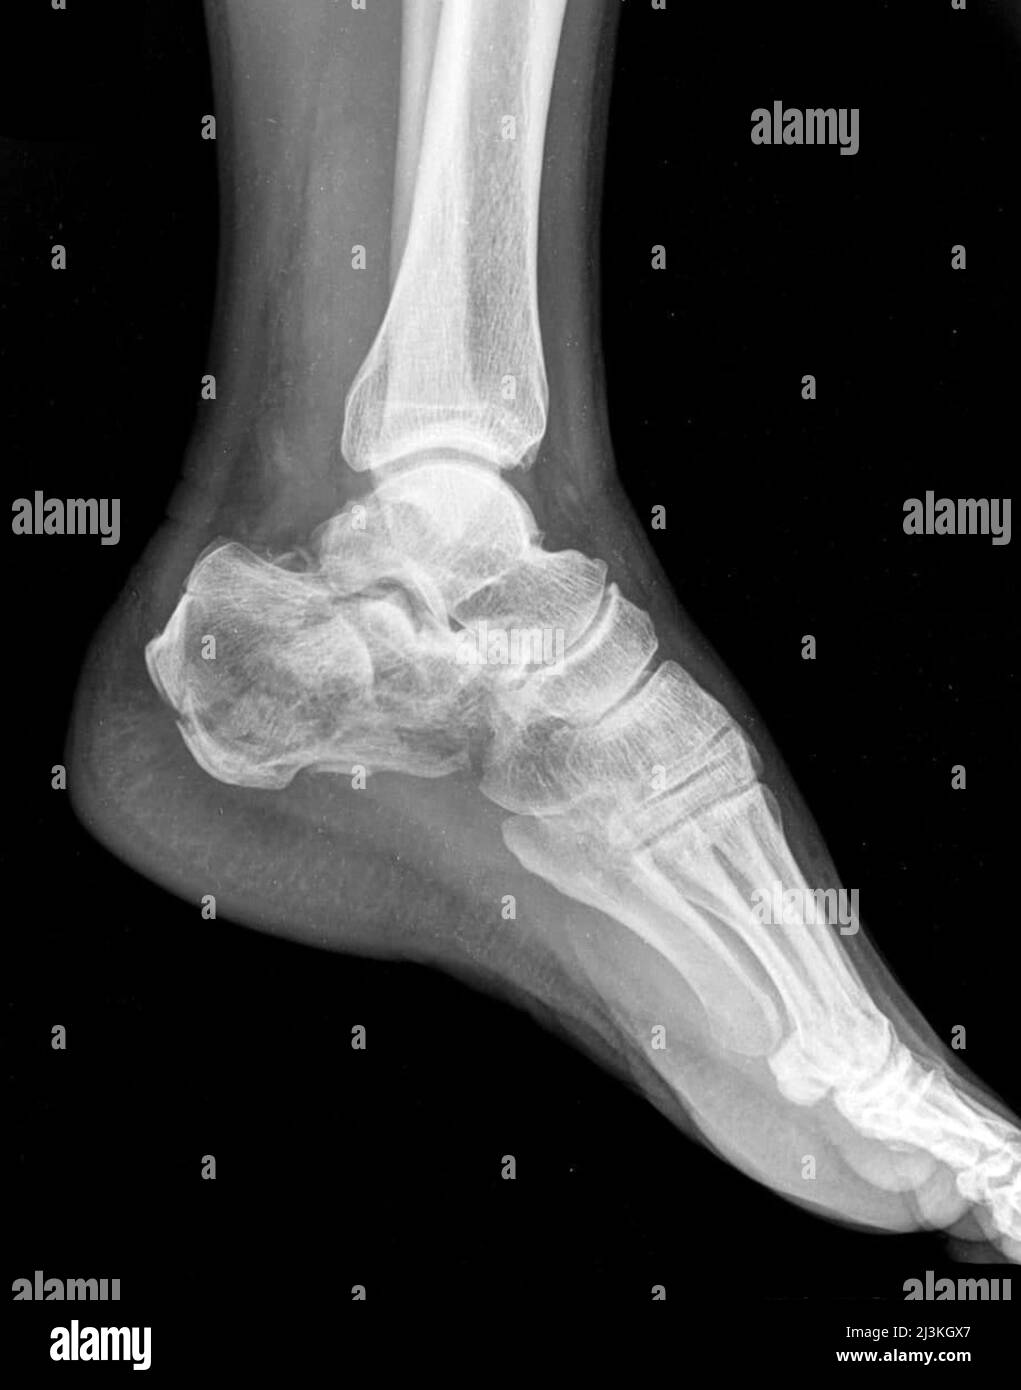

xray of a man's foot showing a fracture of the heel Stock Photo Alamy Fractured Heel Bone Calcaneus fracture is a broken heel bone. Find out how surgery can restore the normal anatomy and function of the heel and subtalar joint. Learn about the causes, symptoms, diagnosis, and treatment of calcaneus fractures, which are painful and disabling injuries to the heel bone. It helps you walk and connects your calf muscles to your foot, which lets you. Fractured Heel Bone.

Fractured Heel, Xray Stock Image C027/2614 Science Photo Library Fractured Heel Bone Calcaneus fracture is a broken heel bone. The calcaneus connects with the talus and cuboid bones. This normally takes six weeks to heal but you may still have pain and swelling for up. Medically reviewed by oluseun olufade, md. Calcaneus fractures may cause heel widening, making it difficult to fit into a shoe. Updated on october 06, 2024. Calcaneal fractures. Fractured Heel Bone.